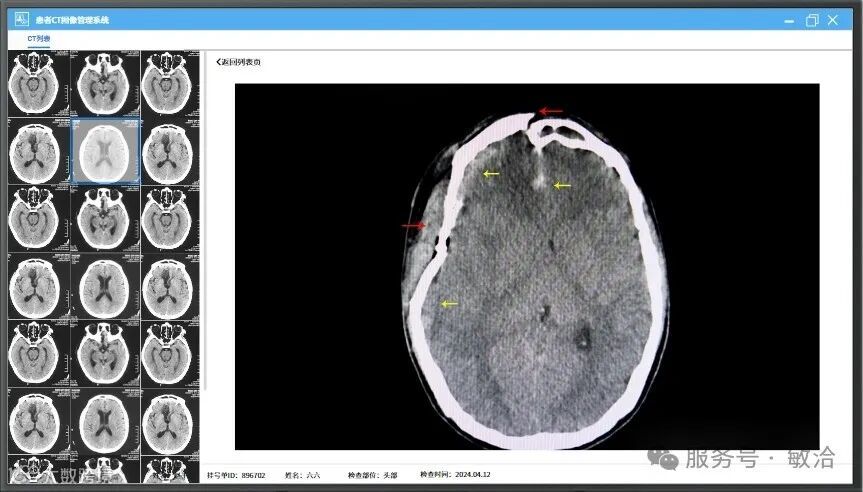

超声聚焦设备,主要分为患者管理系统、CT管理系统、治疗计划系统和设备控制系统。通过前三个系统操作,生成治疗计划。医生输入挂号单ID后,软件获取到治疗计划信息,以表格形式展现在软件界面上,软件默认按获取到的靶点顺序依次进行治疗。医生可以点击选择任一个靶点立即进行治疗。该软件为医生提供了工具来制定和优化患者的放疗计划,提高治疗效果。